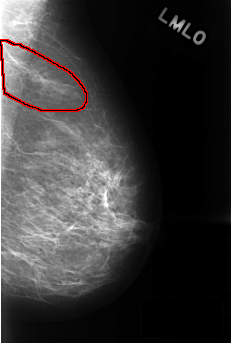

C_0436_1.LEFT_MLO

FILE: C_0436_1.LEFT_MLO.OVERLAY

TOTAL_ABNORMALITIES 1

ABNORMALITY 1

LESION_TYPE MASS SHAPE FOCAL_ASYMMETRIC_DENSITY MARGINS N/A

ASSESSMENT 3

SUBTLETY 5

PATHOLOGY BENIGN_WITHOUT_CALLBACK

TOTAL_OUTLINES 1

BOUNDARY